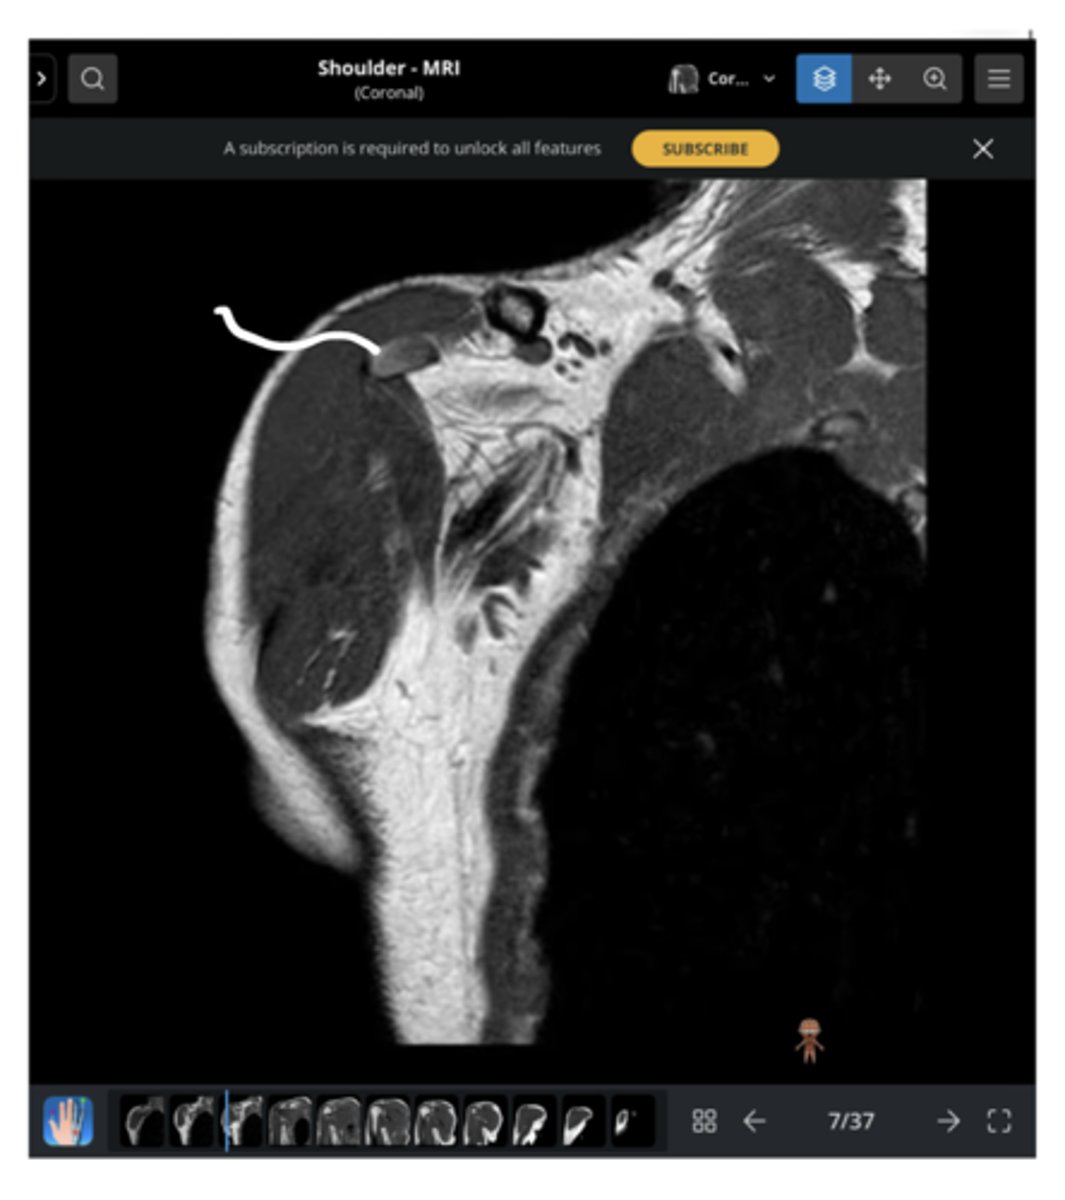

Anterior coronal view of the shoulder -- key to setting this image up is finding the coracoid process, which is NOT present on the back side

What type of view is this? Anterior vs. posterior? How do you know?

Right where the pointer is -- this is where the supraspinatus attaches to the humerus

If there was a supraspinatus tear, where would you see it? Why?